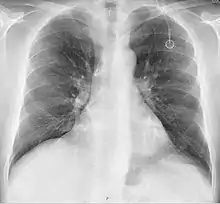

A follow-up on a chest radiograph can immediately detect complications associated with the procedure such as pneumothorax, hemothorax and malpositions of the catheter. However, routine chest radiography is not needed due to the low complication rates associated with the procedure. The chest radiograph is only done if there is clinical suspicion of a complication.[4]

The incidence of catheter fracture is 2.3%. The fracture can be due to "pinch-off syndrome" when the vein and the catheter is compressed when passes between the clavicle and first rib before turning 90 degrees into the superior vena cava. Fractured catheter component can dislodge most commonly into pulmonary arteries (35%), right atrium (27%), right ventricle (22%), and superior vena cava and peripheral veins (15.4%).[5]

Malpositioning of the catheter happens in 0.1 to 5.6% of the time. This can be due to malposition within or outside the superior vena cava. Causes includes: unexpected branches of the veins, vessel angulations, vein stenosis or venous tortousity.[5]

- Pneumothorax: Attempts to gain access to the subclavian vein or jugular vein can injure the lung, potentially causing a pneumothorax. If the pneumothorax is large enough, a chest tube might need to be placed. In experienced hands, the incidence of this complication is about 1% when accessing the subclavian vein. When accessing the jugular vein the pneumothorax rate is virtually nonexistent.